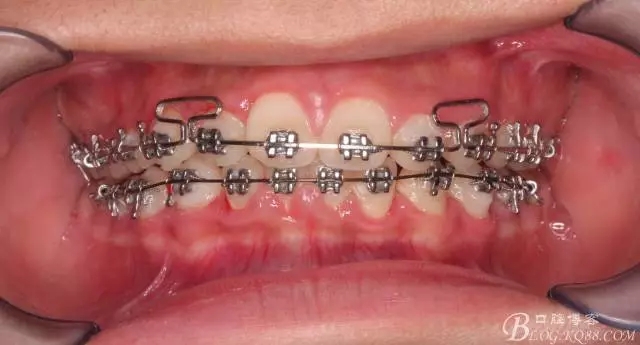

佩戴三個月的FR2, 效果奇佳!前牙基本達到淺覆蓋,淺覆合!接下來進入二期直絲弓固定正畸,排齊階段!

接下來盡管配合些雙側(cè)后牙對角牽引,咬合關(guān)系依,不盡人意。

下頜配合多曲方絲,三角牽引,調(diào)整咬合。